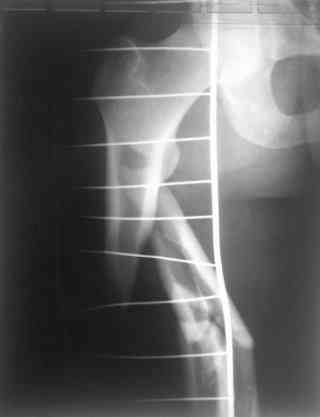

молодй человек 26лет получил С3-перелом правого бедра и легкую черепно мозговую травму (сотрясение головного мозга). Через неделю (противошоковые мереприятия и скелетное вытяжение выполнялось в ЦРБ)оперирован: БИОС бедра стержнем СнМ, Польша. Выписан со швами на амбулаторное лечение по месту жительства в г. Ижевск.Через 1месяц главным врачом больницы, со слов пациента, предложен реостеосинтез пластиной "соберем кость".

одна проблема в моей компьютерной неграмотности(не смог прикрепить снимки), а другая в том, что связь с пациентом потеряна и,насколько я понял в своем регионе ему посоветоваться не с кем, кроме главного врача который отреагировал на выбранную нами тактику так: "там тебя использовали в качестве подопытного кролика...".

Надеюсь сейчас показать перелом, а потом синтез.